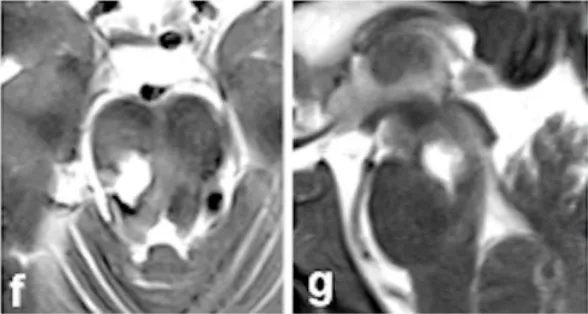

术后影像(图f-g)和术中记录共同证实,病灶已实现完全切除,出血得到彻底控制。令人振奋的是,患者术后恢复迅速,神经功能缺损逐渐改善。经过规范康复训练和随访,术后6个月时,患者已重新恢复正常生活和工作能力。